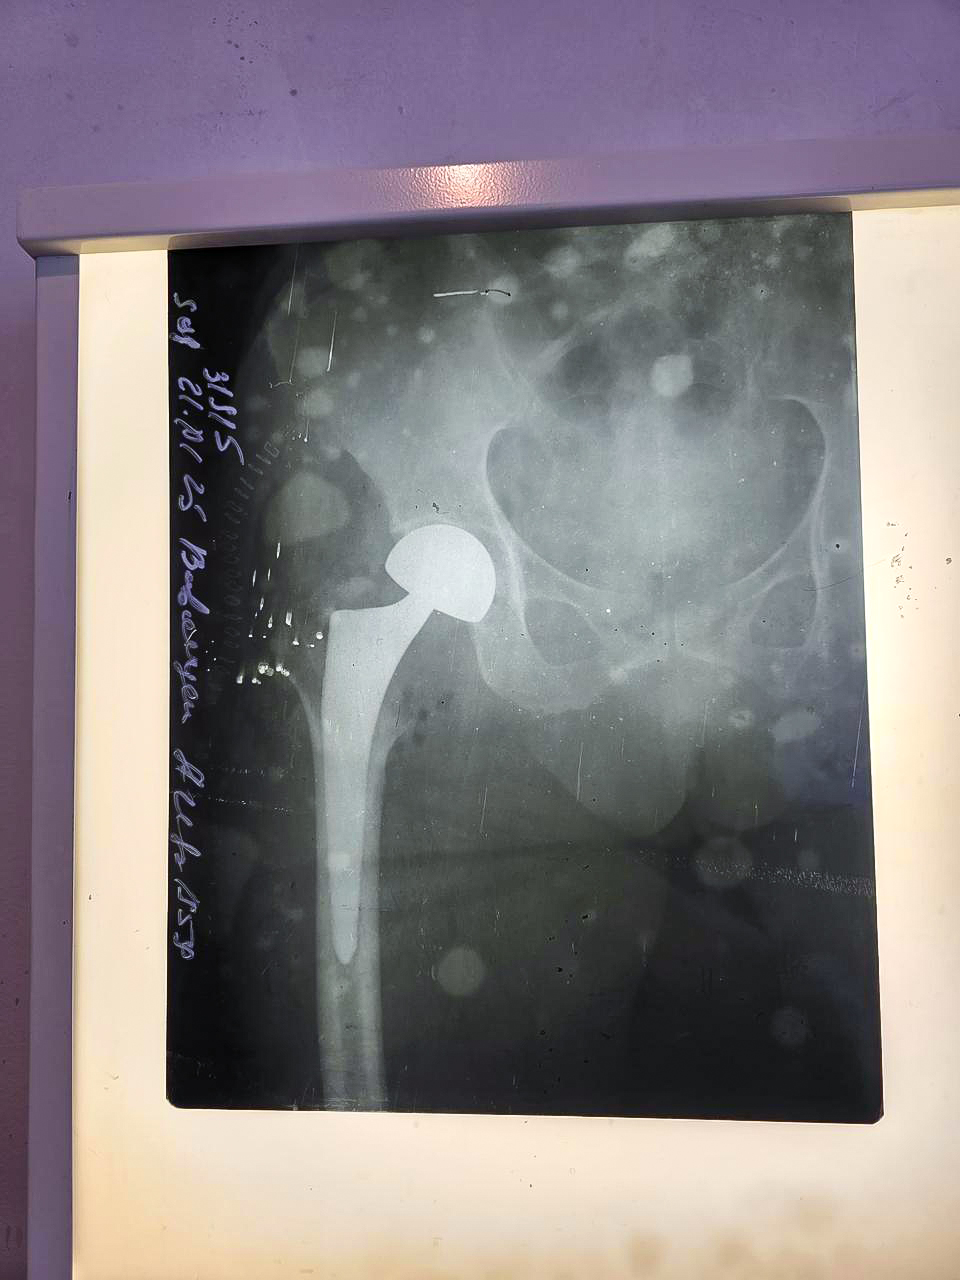

66 yaşlı pasiyent üzərində həyata keçirilmiş bud-çanaq oynağının total artroplastikası (endoprotez) əməliyyatı icbari tibbi sığortanın Xidmətlər Zərfi çərçivəsində qarşılanıb.

Yıxılma nəticəsində sağ bud sümüyünün boyun sınığı diaqnozu ilə müraciət edən pasiyentə müvafiq müayinələrdən sonra sağ bud sümüyünün boynunun subkapital sınığı diaqnozu təyin olunub və cərrahi əməliyyata qərar verilib.

Əməliyyat xəstəxananın Travmatologiya-ortopediya şöbəsinin müdiri, ortoped–travmatoloq Turan İskəndərzadə tərəfindən həyata keçirilib. Əməliyyatdan sonra pasiyentə zəruri tibbi xidmətlər göstərilib. Hazırda onun müalicəsi davam etdirilir, vəziyyəti stabildir.